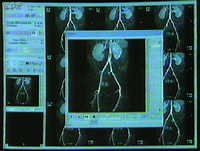

Durchblutungsstörungen in den Beinen lassen sich jetzt entscheidend besser erkennen, als bisher. Ein neues Gerät - der sog. Mobitrak - macht’s möglich. Für den Patienten jetzt ohne Strahlenbelastung, für den Arzt dadurch jetzt optimale Untersuchungsergebnisse. Eine neue Methode, vorgestellt erstmals auf dem Amerikanischen Röntgenkongress in Chicago.

„...45 Minuten und der Patient kann wieder nach Hause gehen. Ein weiterer Vorteil, die Ärzte gewinnen zusätzliche Informationen. Im Computer können die Arterien sogar dreidimensional dargestellt und von allen Seiten begutachtet werden. Damit läßt sich die ärztliche Diagnose verbessern. Alles in allem braucht es weniger Laborarbeit und weniger Personal. Die Untersuchung spart Geld, auch für die Krankenkassen eine Methode mit Zukunft.“